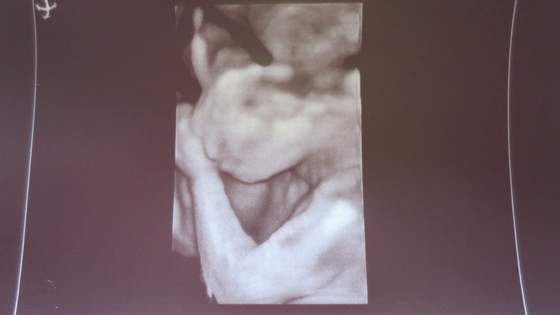

Ja dziś po mega ekscytującej wizycie bo czekałam na usg w 3D z ogromną niecierpliwością i podnieceniem.

No i chwalę się zdjęciami aczkolwiek co do zdjęć w 3D pokładałam dużo większe nadzieje. Szału nie było ale rzecz jasna bajer.